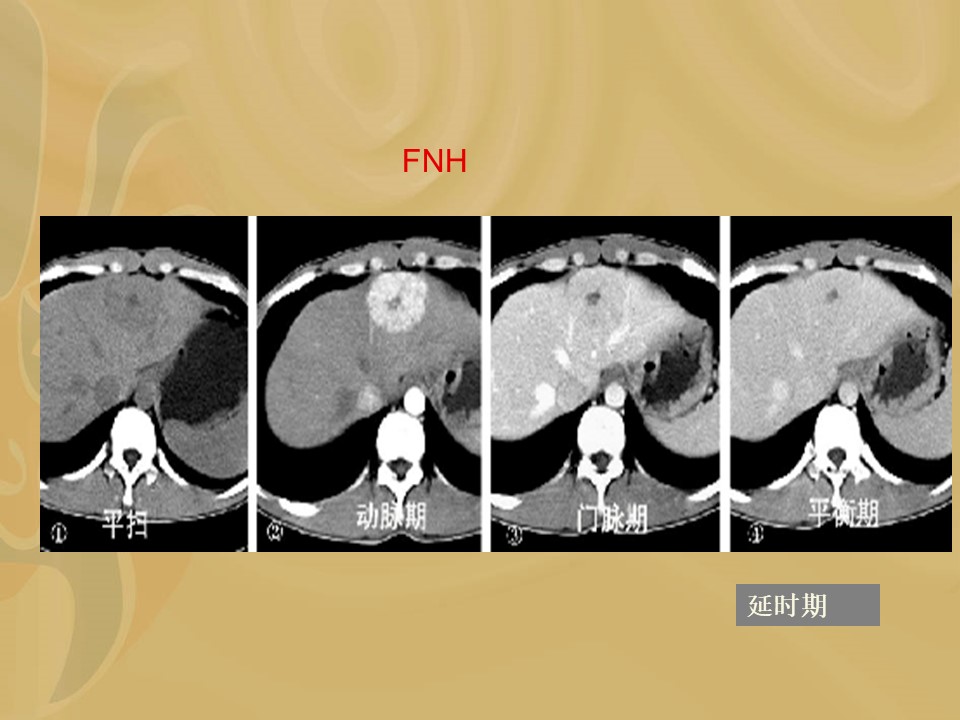

“肝脏富血供病变的诊断及鉴别诊断PPT” 的相关文章